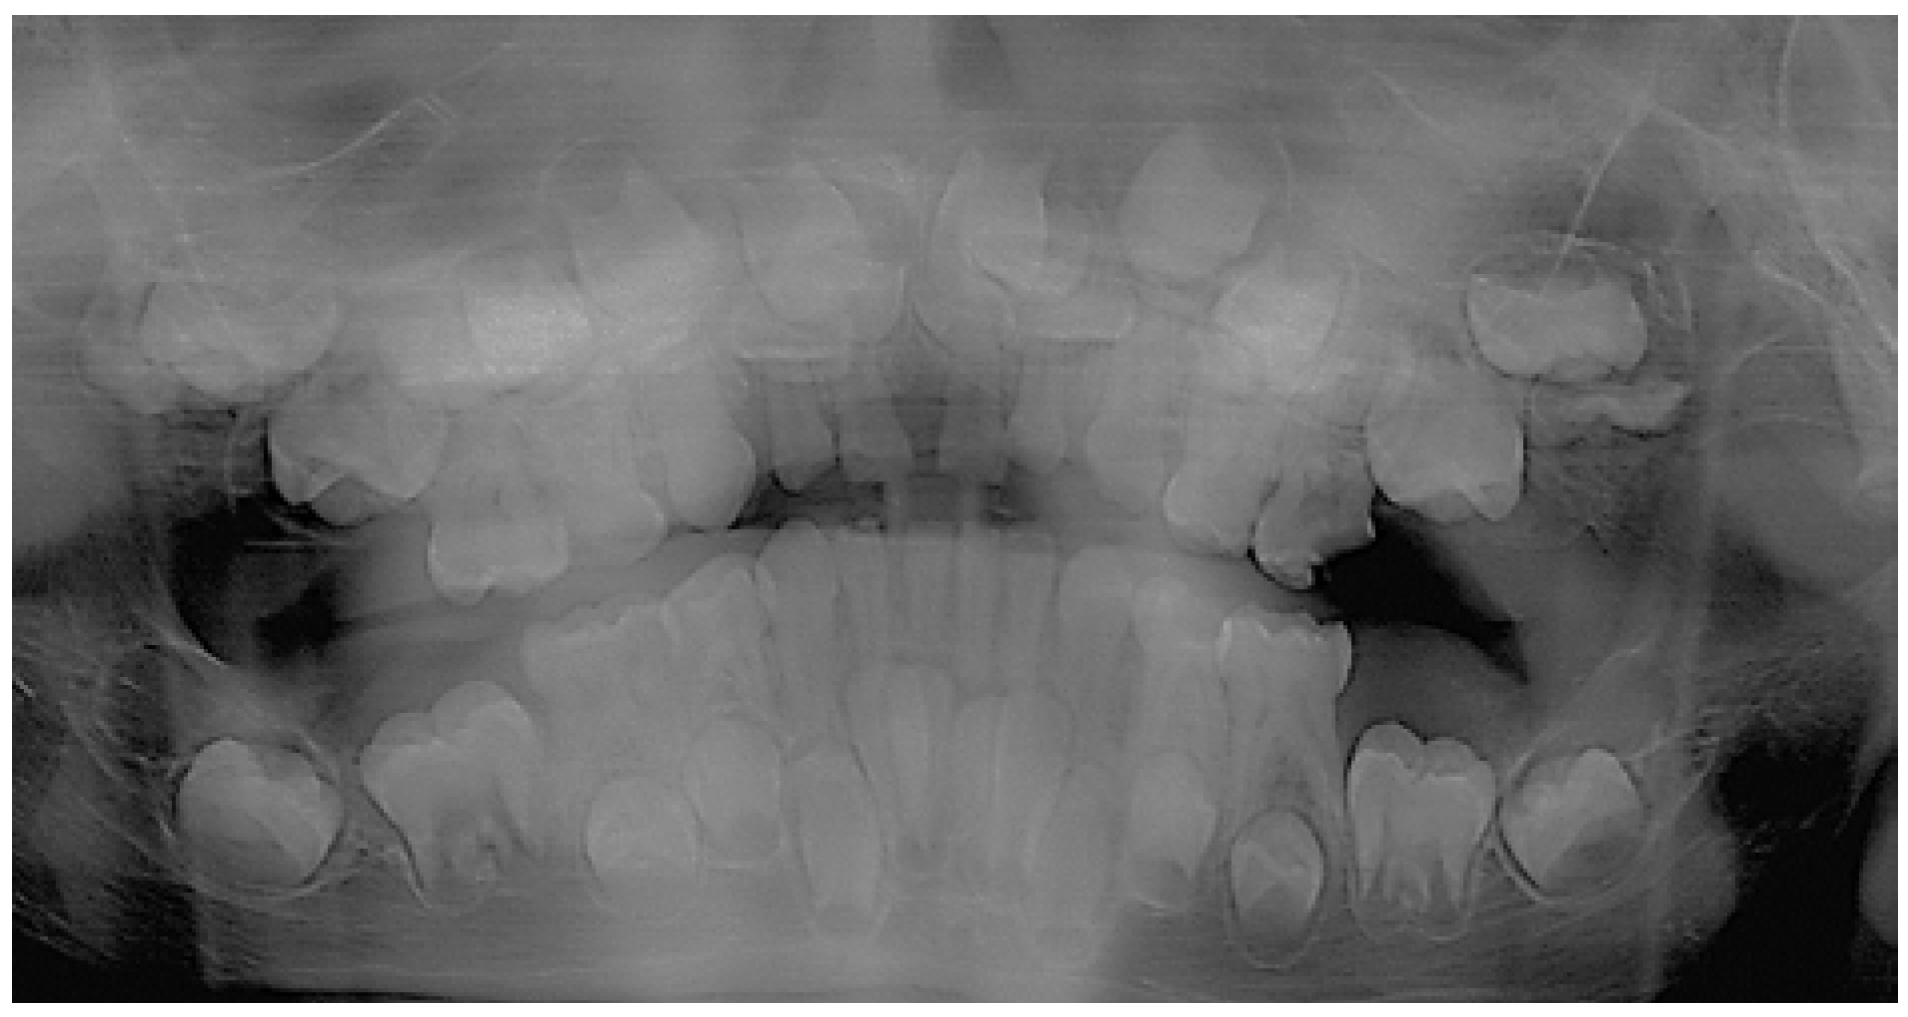

On the panoramic radiographic image (OPG) taken in April 2013 (Figure 1.) there was a finding of over-retained deciduous teeth with unresorped roots. The dental age was estimated according to the Demirjan method, 4,6 years in the upper dental arch and 6,9 in the lower. Three supernumerary teeth were present in the upper jaw, and two in the lower, displacing the developing permanent teeth and obstructing their eruption. All regular permanent teeth buds were in place, some of them were retarded in eruption also because of a lessened eruptive potential. There was a serious (approximately 3 years) delay in the root development of the permanent teeth. The dental age was estimated according to the developmental stages of the roots of permanent teeth and resorption stages of deciduous predecessors – the Demirjan method [19,22].

The three-dimensional (3D) reconstruction of the CBCT x-ray, taken in May 2013 revealed three more supernumerary empty tooth crypts in the upper jaw and proved the two supernumerary teeth in the lower. The patient had had 8 supernumerary teeth at that time. (Figure 1.,6.,7.)

Figure 1. The initial OPG x-ray of the patient (2013).